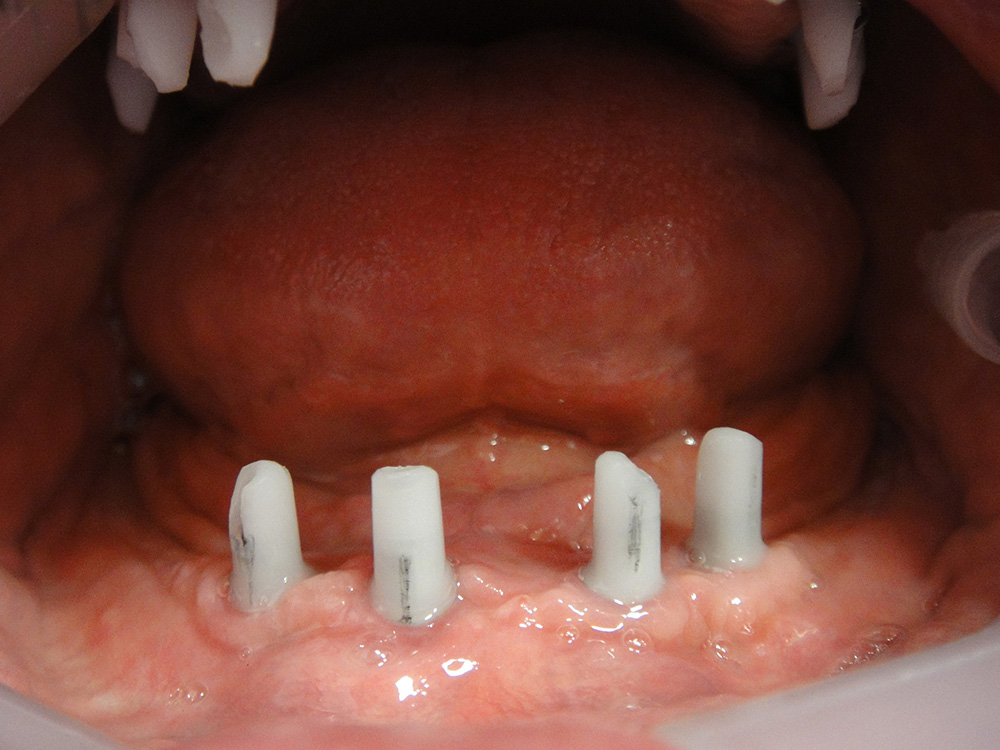

Protesi fissa in mandibola avvitata su impianti dentali

Dopo

Arcate dentali montate su impianti dentali. Uomo di 70 anni.